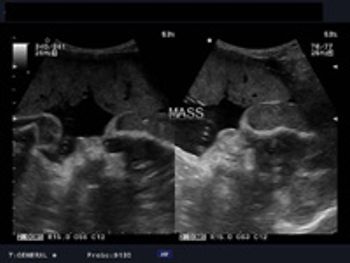

What is your diagnosis of this 36 week old fetus with cardiomegaly?